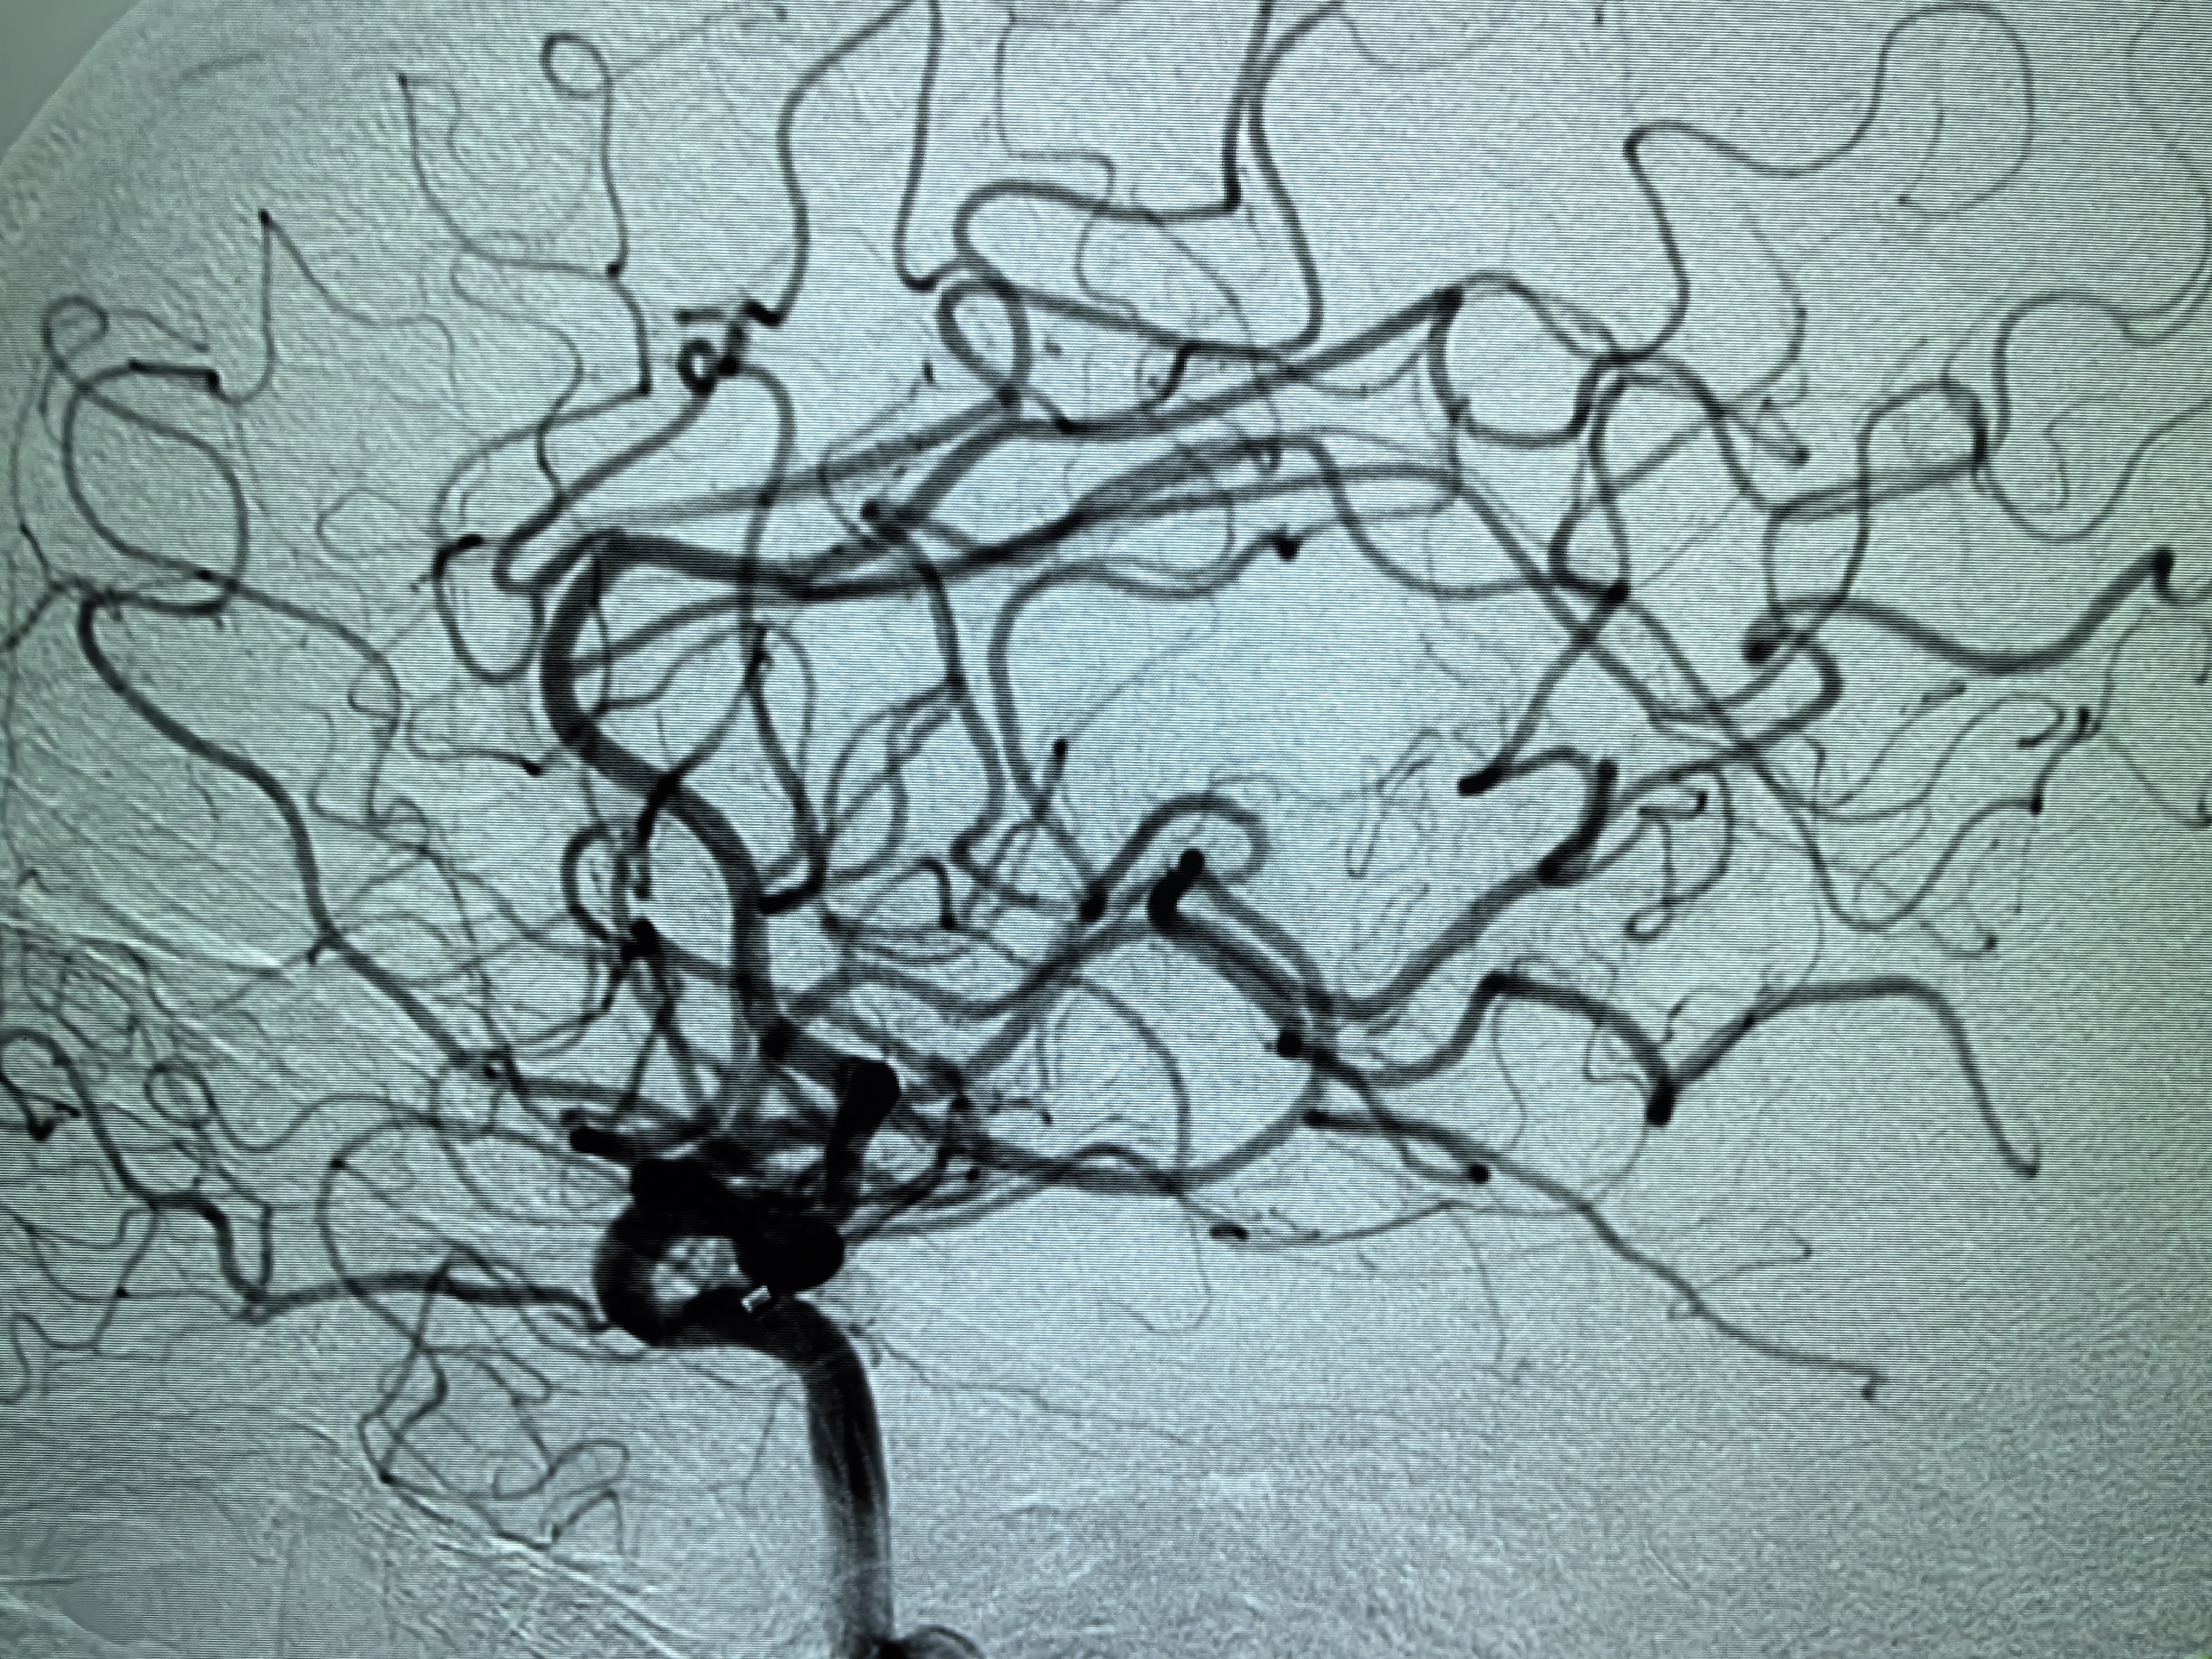

患者术前明确右侧颈内动脉系统栓塞,遂快速建立8F导引导管+CAT6中间导管取栓路径,微导丝携微导管顺利通过病变。

3、SWIM技术有效开通颅内大负荷血栓后应积极预防再灌注损伤,积极控制脑水肿。